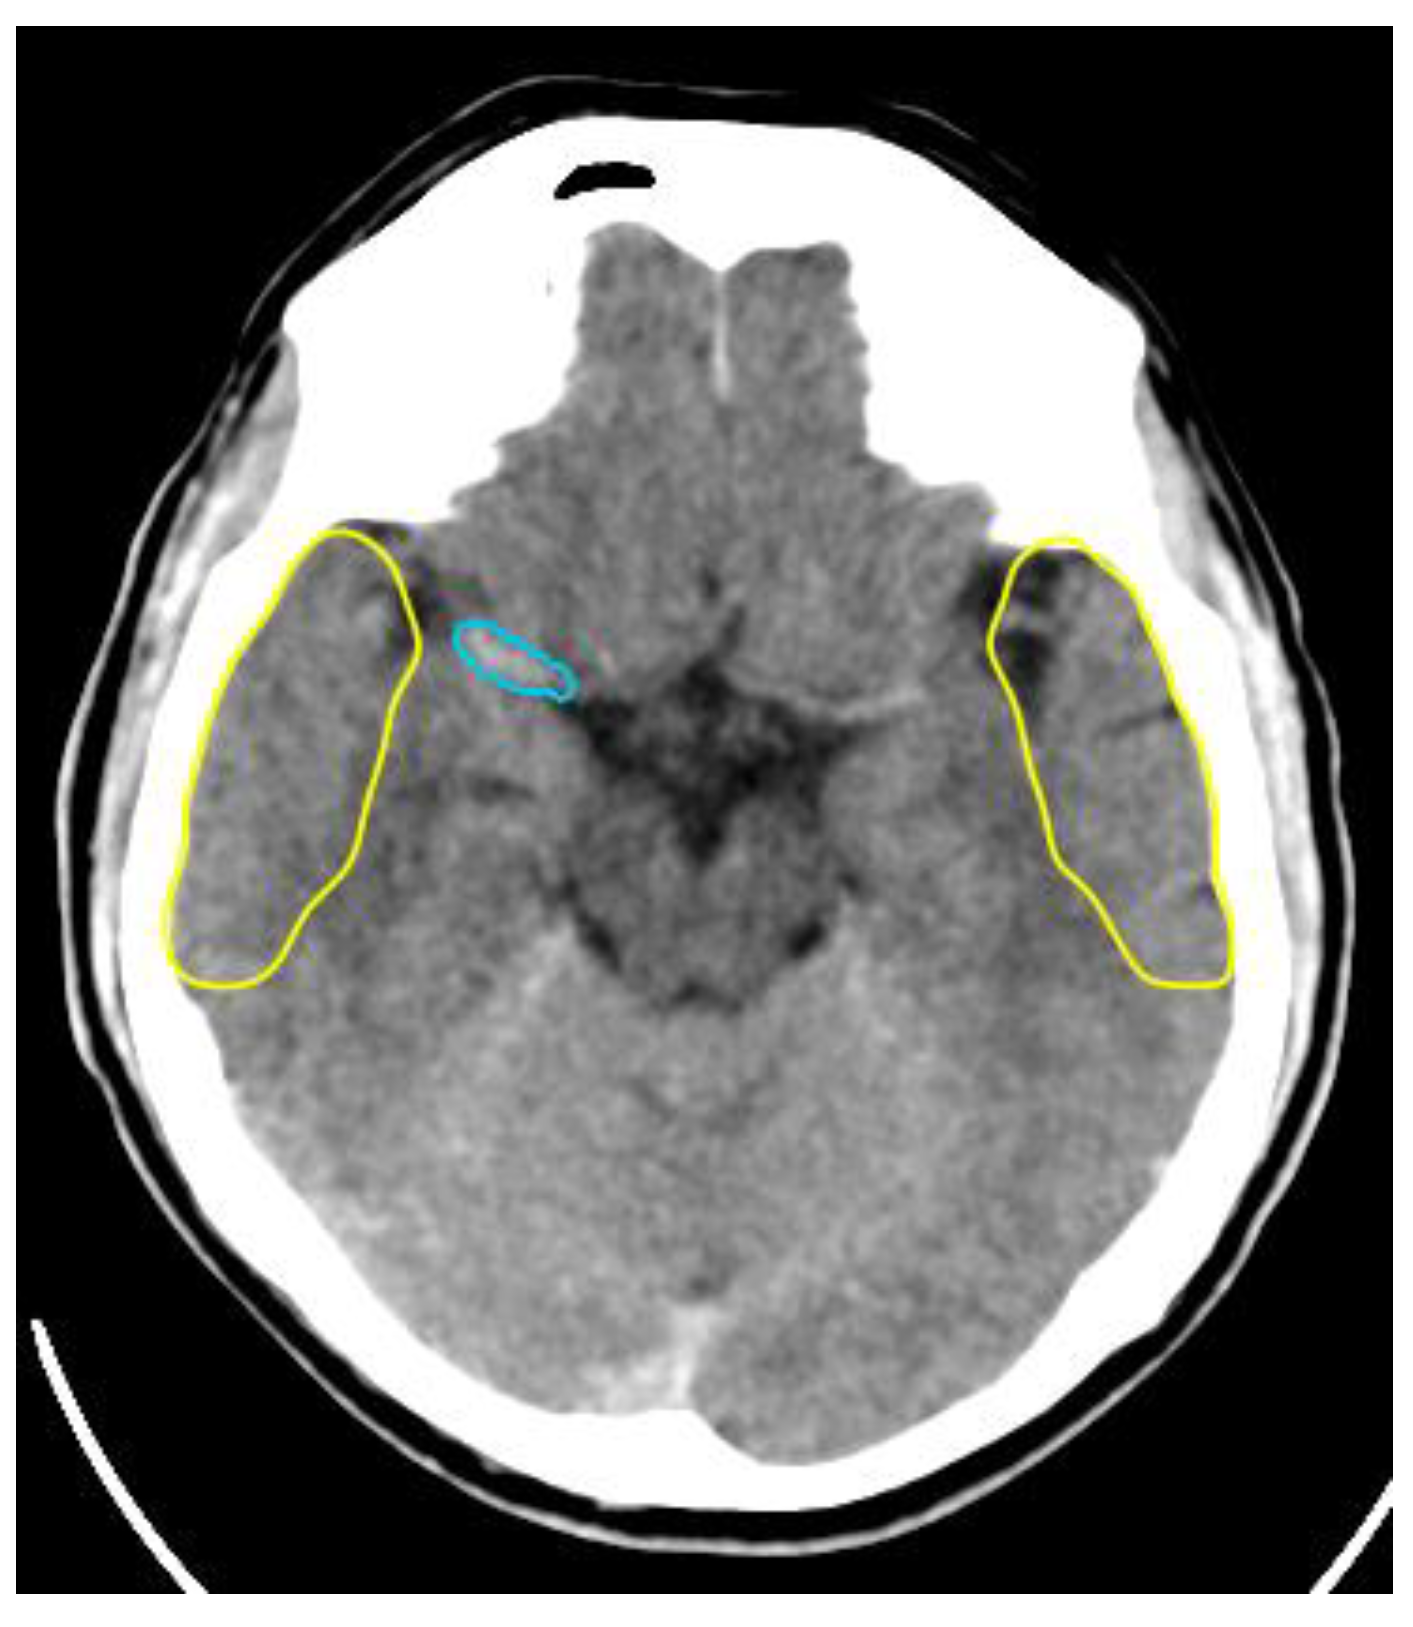

ASPECTS

Collateral Score